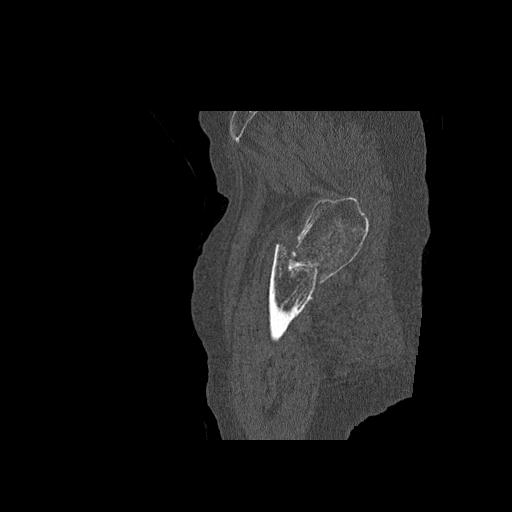

110286 2/17 股関節 2R 74歳女性 右人工骨頭